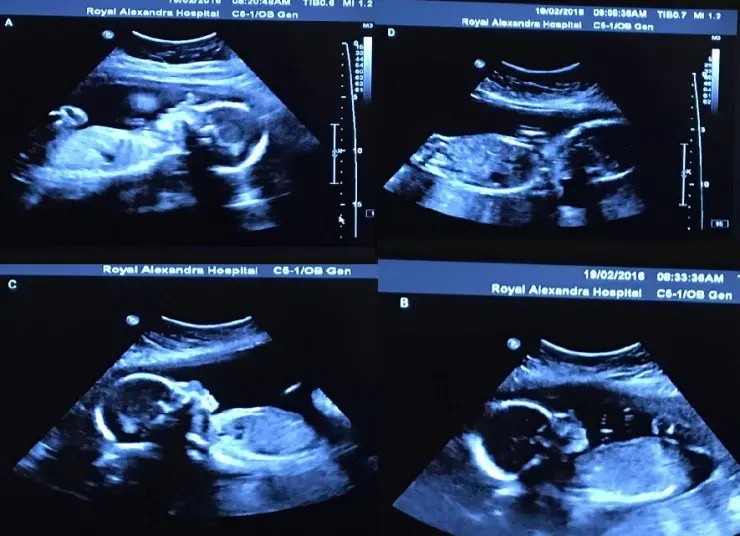

Bethani and Tim Webb, a Canadian couple from Alberta, have desired to start a family for a long time. They eventually succeeded, and the doctor gave them some vital news while they were having a normal check-up. According to the Daily Mail, such incidents are extremely rare.

Bethani, the young mother, found out she was having four girls instead of one. She initially mistook the doctor’s remark as a joke about her. “I couldn’t believe what I was hearing; I was stunned. To be honest, I thought the doctor was joking when he said that. I couldn’t believe what I was hearing “, the young mother remarked on social media.

Given that neither Bethani nor her boyfriend comes from a family with such a trait, Bethani wondered how they managed to conceive four girls in their pregnancy. The children, Abigail, McKayla, Grace, and Emily, were born naturally and via cesarean section.